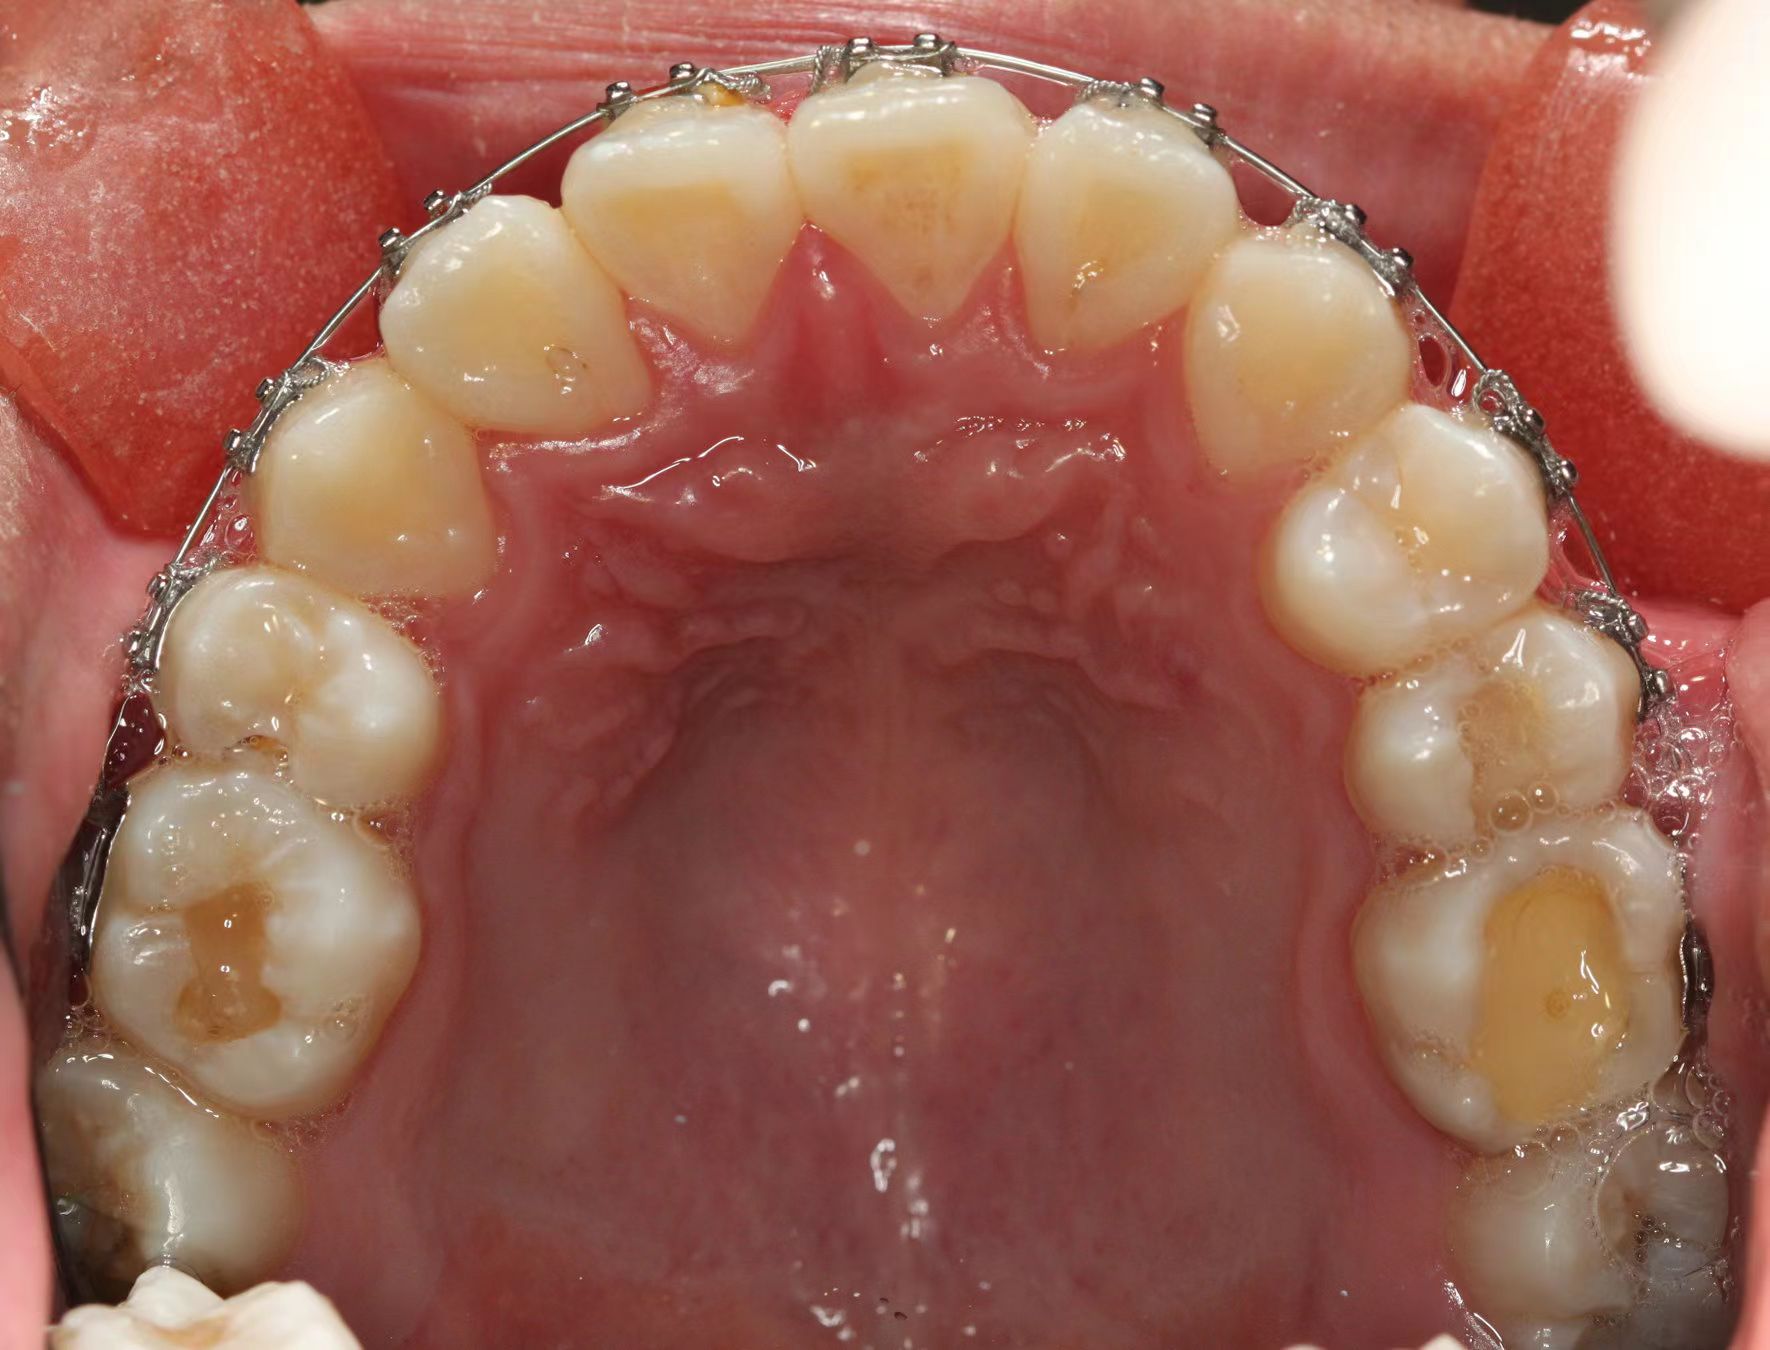

情况:不接受外科手术,在当地做了1年半的矫治,遇到困难无法进行。由外地正畸同行推荐来上海寻求非手术矫治的二手病例。武广增老师接收时的错合畸形情况,呈现严重的骨性反合偏合及侧方开合(图1-图10)。由于推荐其去口腔医院接受正颌外科手术遭到拒绝,武广增老师通过专业的检查、分析,制定一套详细的治疗计划,采用了磨牙推进器技术、武式辅弓技术等特色正畸手段获得明显效果(图2-1~图2-9)。治疗结束后也拍摄了相关照片(图3-1~图3-9)。

矫治前

图4